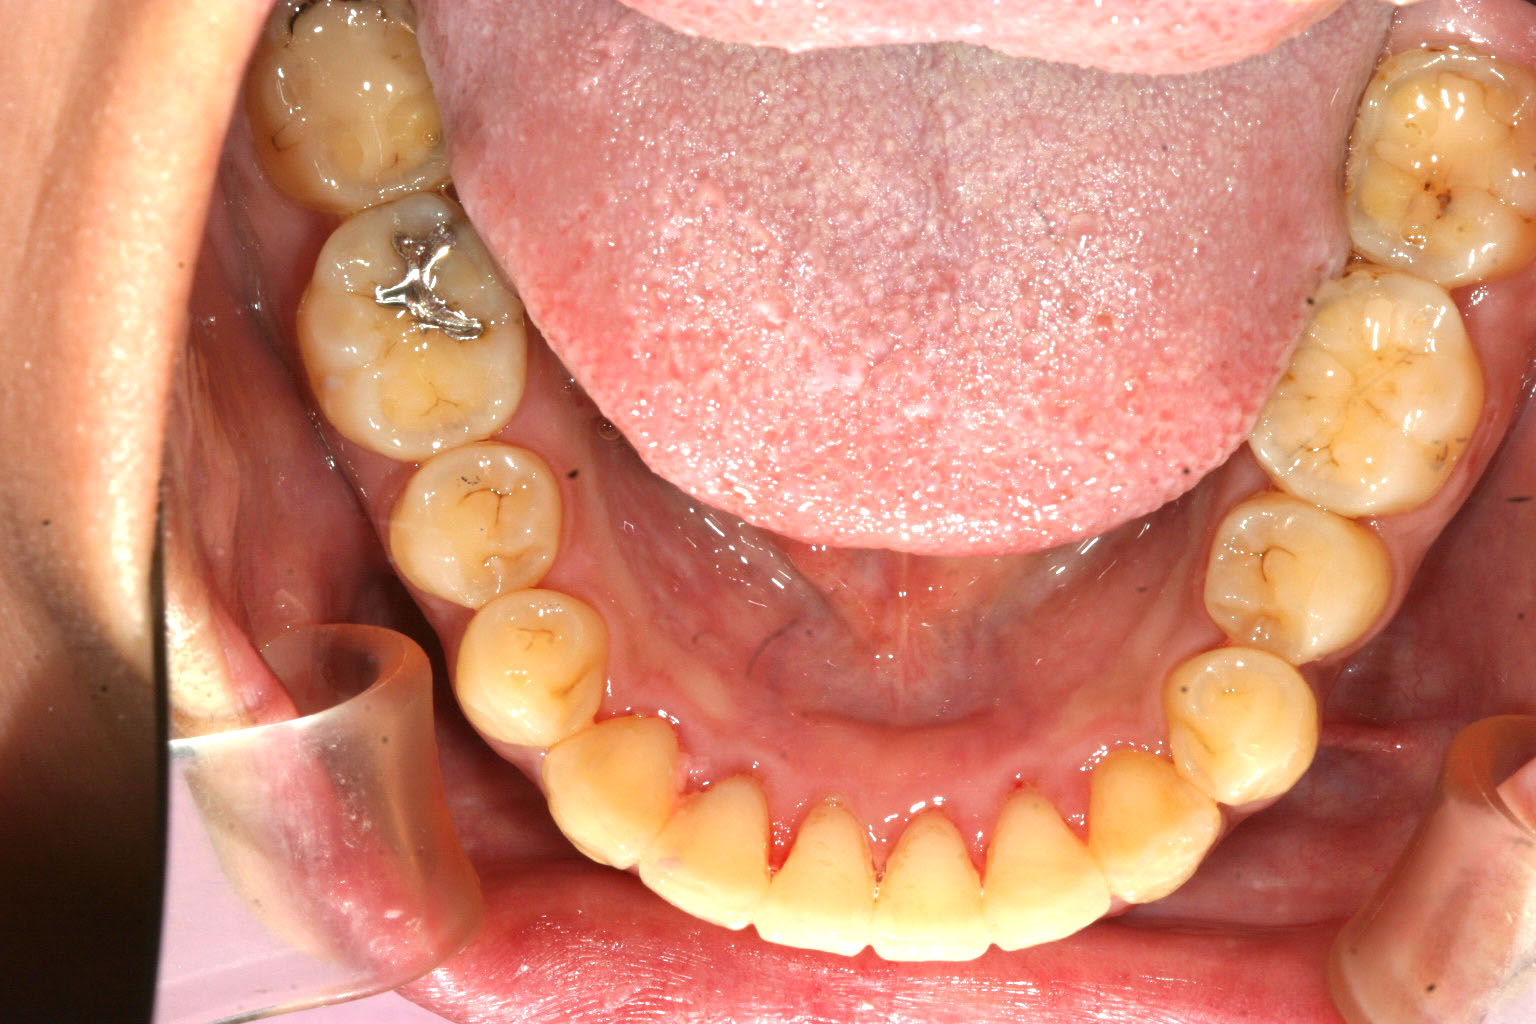

下顎にも少し叢生が見られます。

下顎も綺麗に並びました。